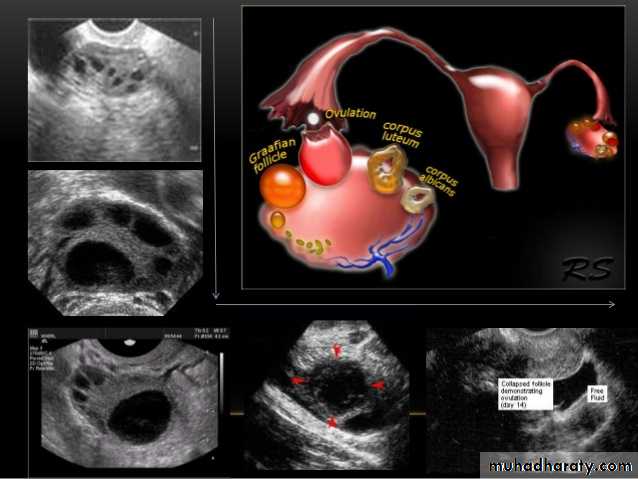

Ovarian cysts :

Ovarian cysts are commonly encountered in gynecological imaging, and vary widely in etiology, from physiologic, to complex benign, to neoplastic.

Small cystic ovarian structures should be considered normal ovarian follicles unless the patient is pre-pubertal, post-menopausal, pregnant, or the mean diameter is >3.0 cm

Polycystic ovarian syndrome (PCOS) is a chronic anovulation syndrome. Sonographic findings alone are not specific, and the diagnosis is made on the combined clinical, biochemical and sonographic grounds

The classic triad of PCOS is:

oligomenorrhea

hirsutism

Obesity

Ovaries

may show sonographic features of polycystic ovaries

bilateral enlarged ovaries with multiple small follicles: 50%

increased ovarian size (>10 cc)

12 or more follicles measuring 2-9 mm

follicles of similar size

peripheral location of follicles: which can give a string of pearl appearance

hyperechoic central stroma

the ovarian outline may be slightly irregular.